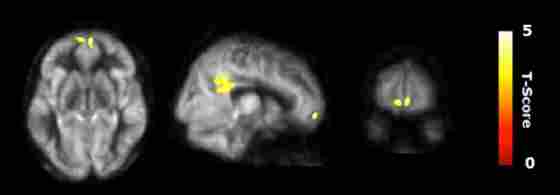

Regional cerebral blood flow (CBF) results. Voxel-based analysis for the interaction contrast described in text, superimposed on an average CBF map of all participants. Both cluster volumes k = 3792 mm3 for posterior cingulate cortex (PCC) and k = 992 mm3 for medial orbitofrontal cortex (mOFC) are significant at an family-wise error correction (FWE) alpha level of 0.05 (k = 784 mm3).